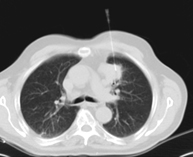

- Tórax- TC Tórax Prueba diagnóstica que consiste en obtener imágenes del tórax de alta definición anatómica (pulmones, corazón, mediastino, grandes vasos, caja torácica, etc.) mediante el empleo de un equipo de TC (Tomografía Computarizada). Dichas imágenes se estudian posteriormente en una estación de trabajo que permite reconstrucciones bidimendionales en diferentes planos del espacio y también reconstrucciones 3D (volumétricas). Algunos estudios requieren el empleo de contraste yodado para mejorar la definición de las imágenes. Prueba diagnóstica que consiste en obtener imágenes del tórax de alta definición anatómica (pulmones, corazón, mediastino, grandes vasos, caja torácica, etc.) mediante el empleo de un equipo de TC (Tomografía Computarizada). Dichas imágenes se estudian posteriormente en una estación de trabajo que permite reconstrucciones bidimendionales en diferentes planos del espacio y también reconstrucciones 3D (volumétricas). Algunos estudios requieren el empleo de contraste yodado para mejorar la definición de las imágenes.

- TC Tòrax Prova diagnòstica que consisteix en obtenir imatges del tòrax d'alta definició anatòmica (pulmons, cor, mediastí, grans vasos, caixa toràcica, etc.) mitjançant l'ús d'un equip de TC (Tomografia Computeritzada). Aquestes imatges s'estudien posteriorment en una estació de treball que permet reconstruccions bidimensionals en diferents plans de l'espai i també reconstruccions tridimensionals (3D: volumètriques). Alguns estudis requereixen l'ús de contrast iodat per millorar la definició de les imatges. Prova diagnòstica que consisteix en obtenir imatges del tòrax d'alta definició anatòmica (pulmons, cor, mediastí, grans vasos, caixa toràcica, etc.) mitjançant l'ús d'un equip de TC (Tomografia Computeritzada). Aquestes imatges s'estudien posteriorment en una estació de treball que permet reconstruccions bidimensionals en diferents plans de l'espai i també reconstruccions tridimensionals (3D: volumètriques). Alguns estudis requereixen l'ús de contrast iodat per millorar la definició de les imatges.